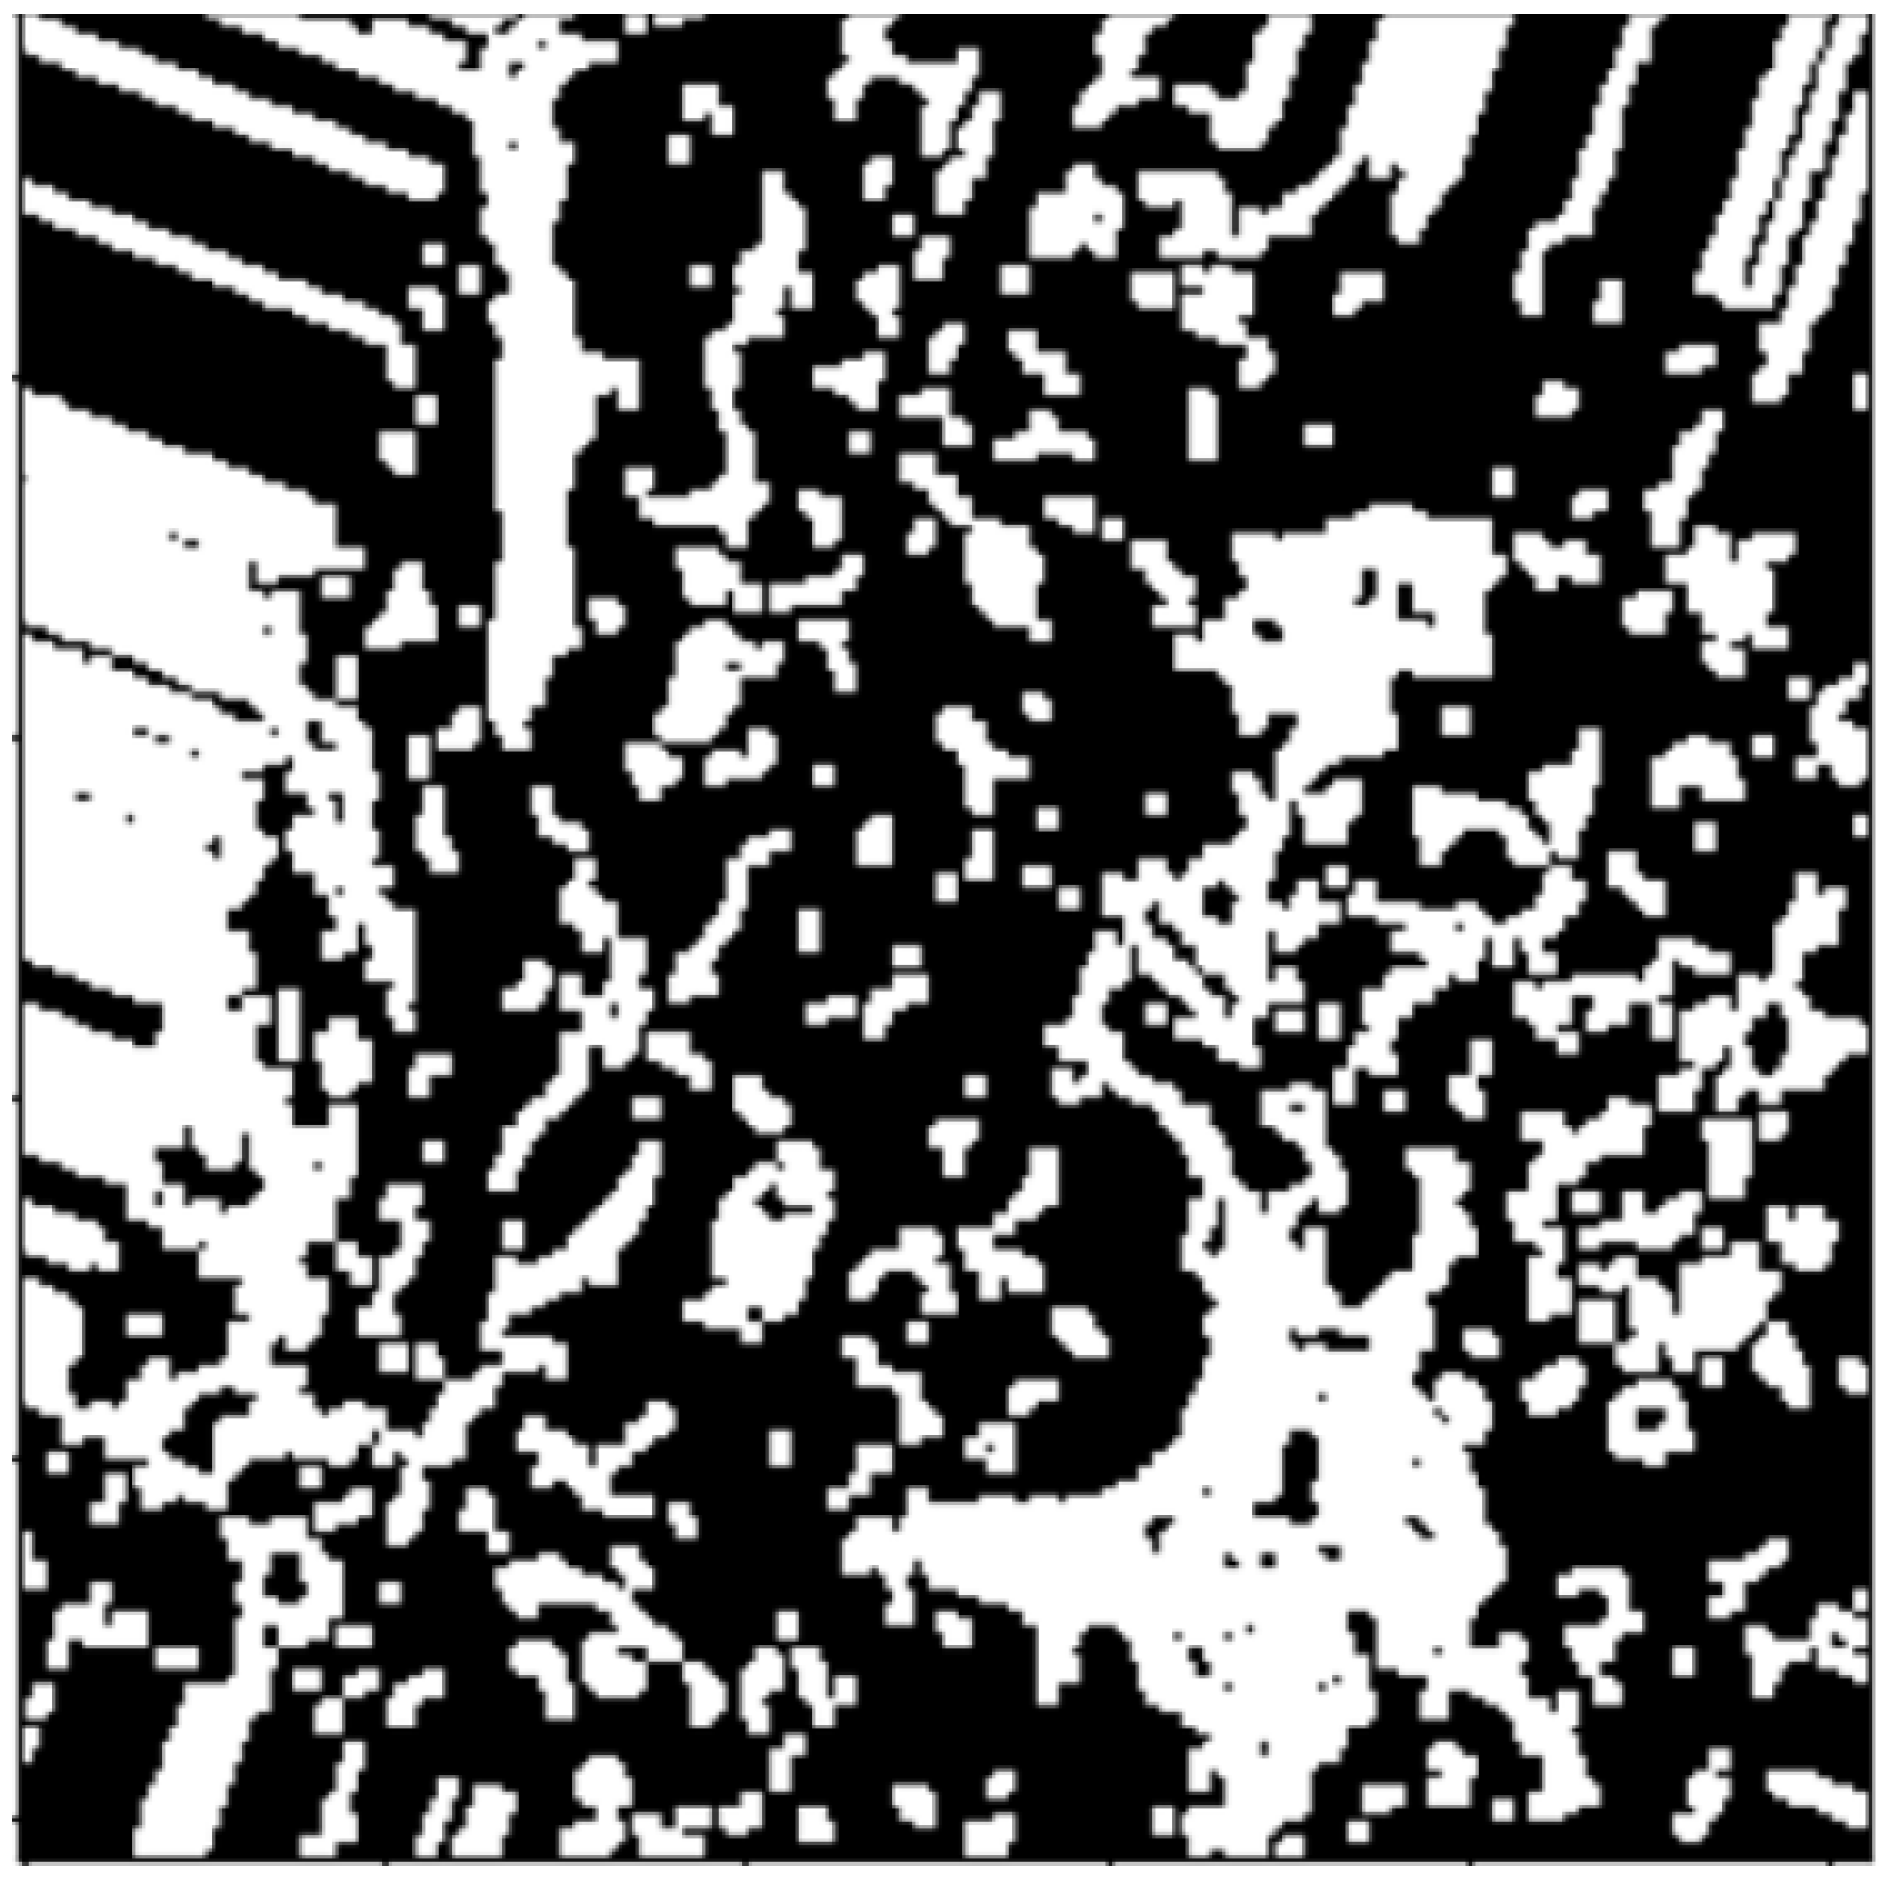

2.2.1. Thresholding

2.2.2. Morphology Operations